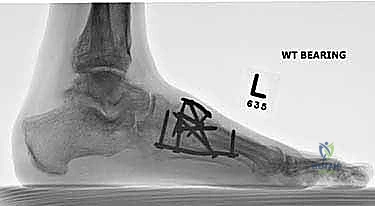

- الأشعة السينية أثناء الوقوف (Weight-bearing X-rays): وهي أهم أداة تشخيصية. الأشعة العادية والسرير فارغ لا تظهر المشكلة الحقيقية؛ يجب التقاط الأشعة والمريض يقف ليتحمل وزن الجسم، مما يظهر الانهيار الفعلي للمفاصل وتضيق المسافات بين العظام.

- الأشعة المقطعية (CT Scan): توفر صوراً ثلاثية الأبعاد للعظام، وهي ضرورية جداً للتخطيط الجراحي الدقيق وتحديد مدى التلف العظمي والزوايا المطلوبة للتثبيت.